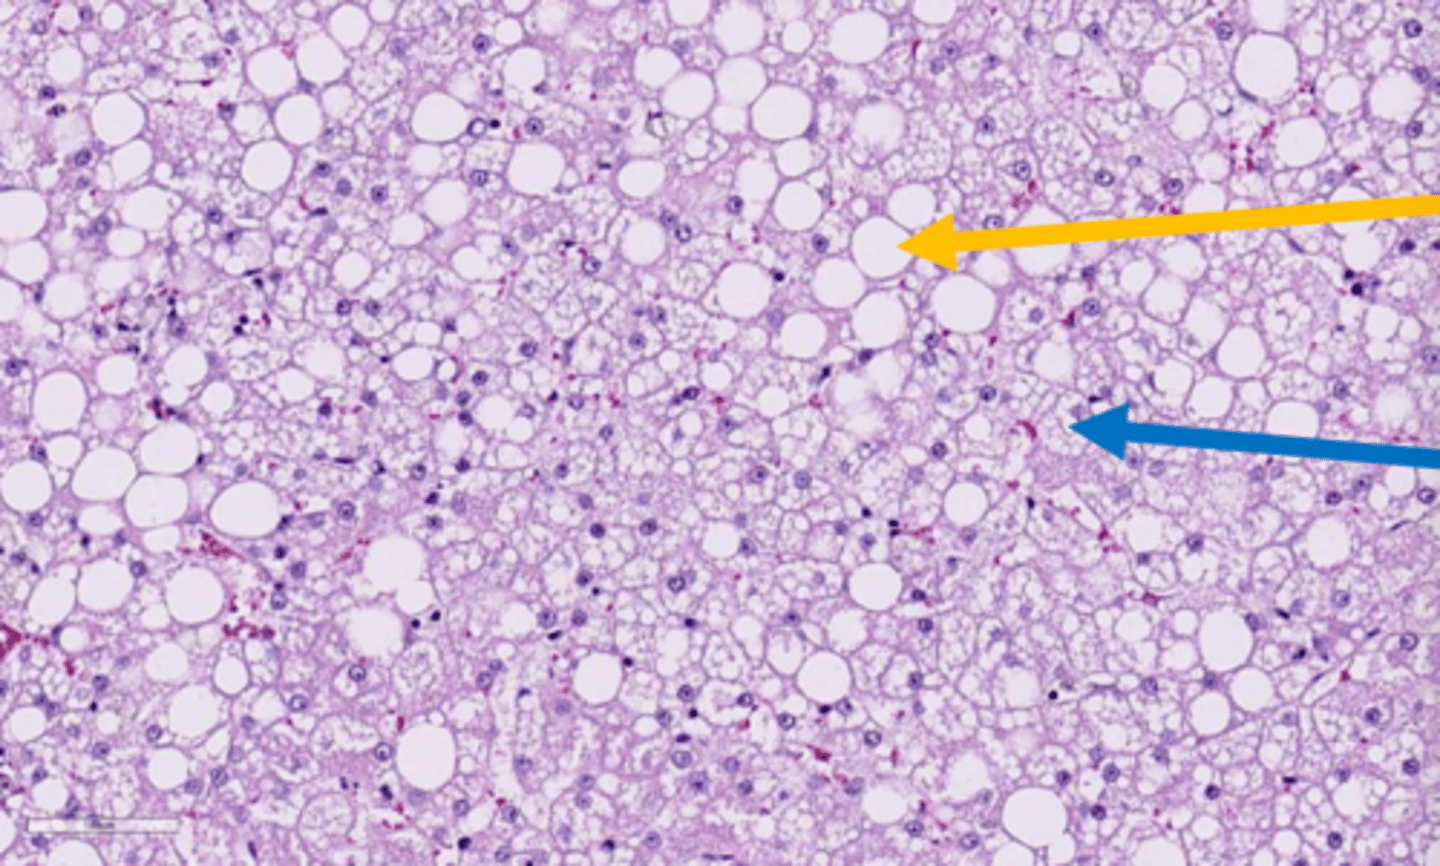

swollen, yellow, greasy texture, maybe friable and floats in formalin, rounded margins

What are the characteristics grossly of an organ with lipidosis?

hepatic lipidosis

grossly.. what is this